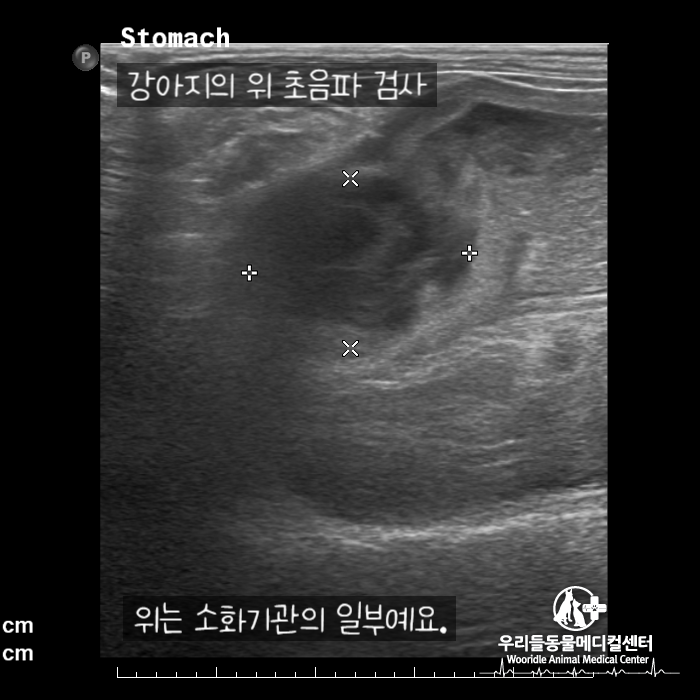

강아지 위의 초음파 검사

종양이 의심되는 부분이 있어서 추가검사에서 CT촬영을 했습니다.